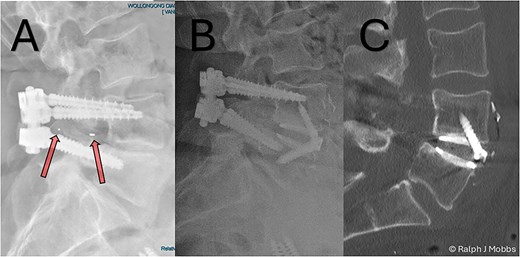

Stage one: anterior lumbar interbody fusion

Day 1 postop ALIF. The PEEK cage can be seen in the canal and paraspinal regions. (A) Axial sequence. (B) Parasagittal sequence.